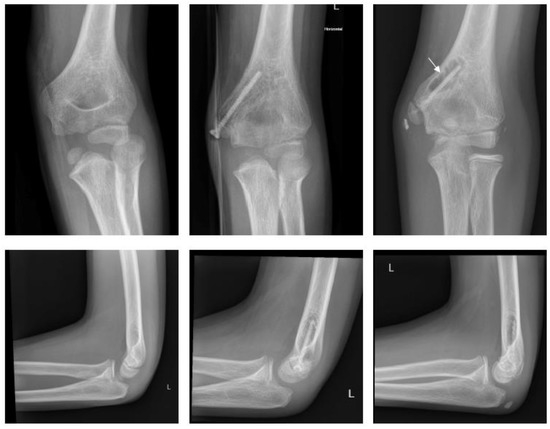

2.4.2. Fracture of the Medial Epicondyle

2.4.3. Fracture of the Lateral Condyle